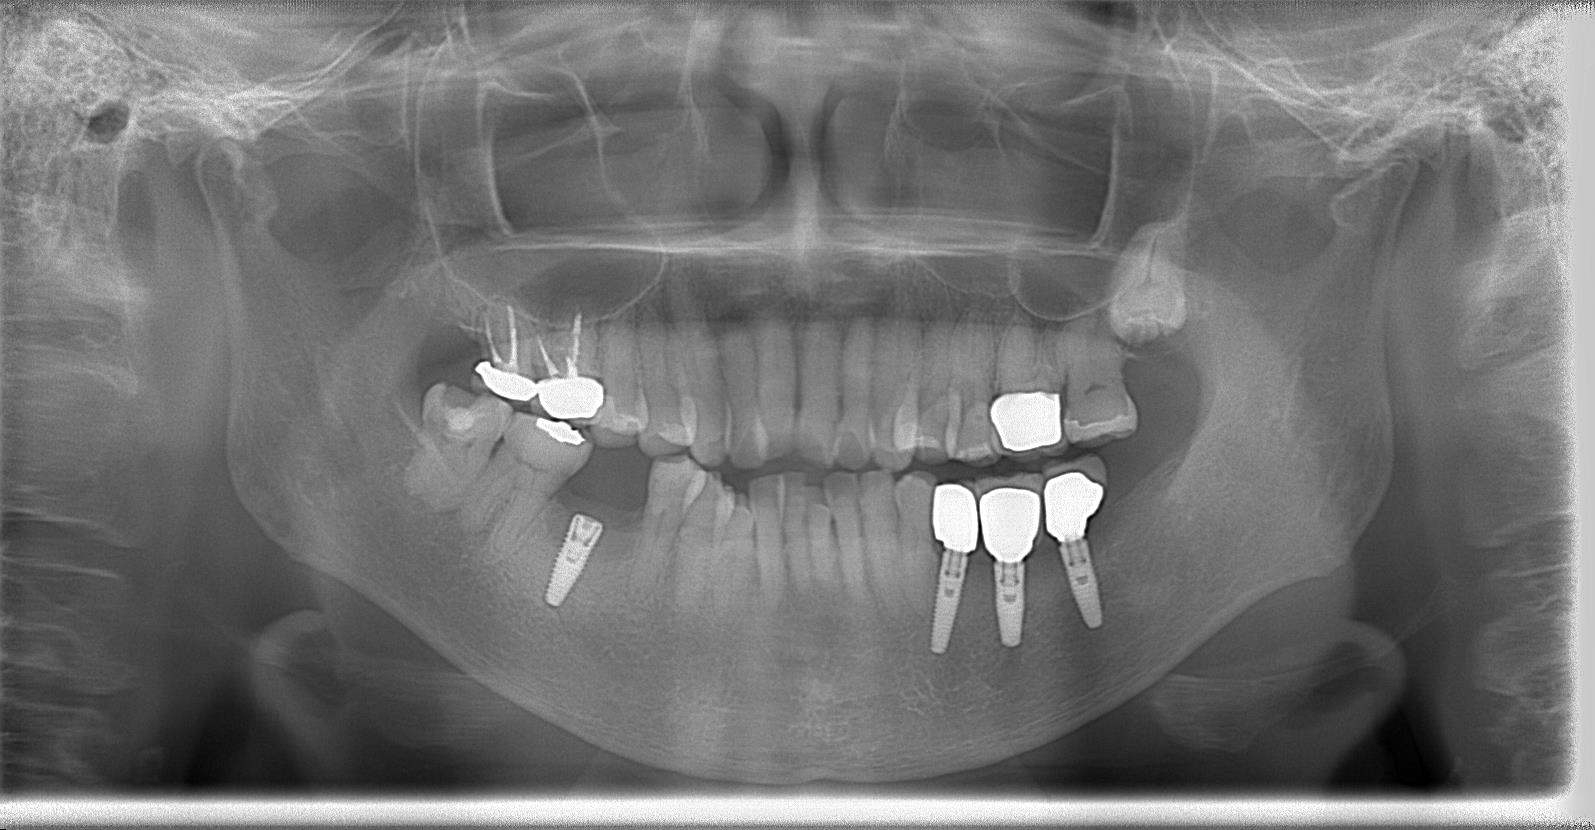

術後パノラマレントゲン写真